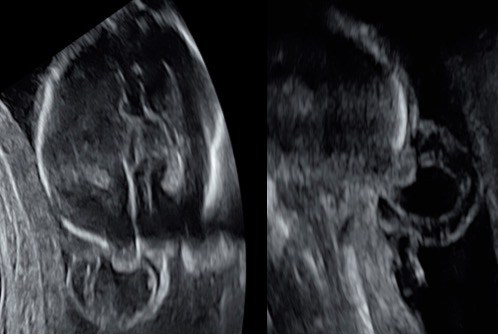

diagnostic

il peut être fait en anténatal, devant une lésion kystique et une microcéphalie.

quand la lésion est petite, elle n’est parfois visible qu’après la naissance.